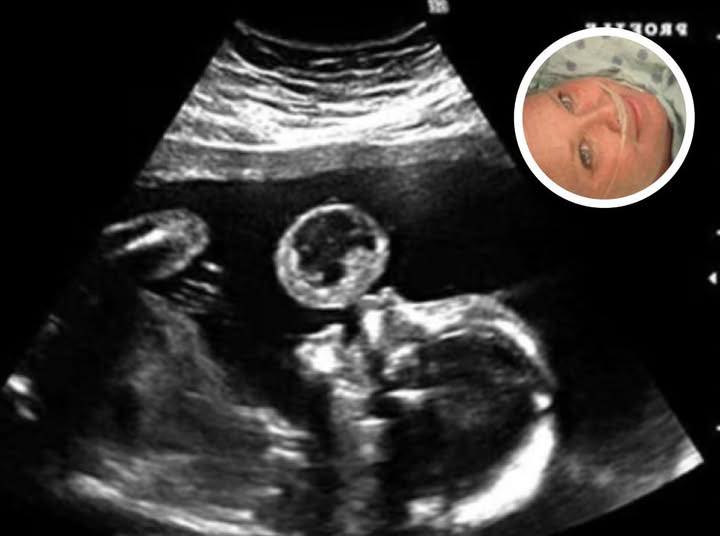

Mom Thinks Her Baby Is Blowing Bubble In Ultrasound, Then Doctors Discover What It Really Is

Tammy Gonzalez, a Miami mother, went in for what she expected to be a routine prenatal ultrasound, but the appointment quickly turned into a moment of fear and uncertainty. Doctors discovered a large, bubble-like mass hovering above her unborn baby’s mouth, something no parent expects to see during a joyful first glimpse. Confused and terrified, Gonzalez asked whether the growth was on her or her baby, hoping for clarity as doctors examined the strange image.

Further evaluation revealed the mass was a teratoma, a rare and potentially fatal tumor that affects roughly 1 in 100,000 pregnancies. The diagnosis came with devastating warnings: the tumor could cause miscarriage, threaten the baby’s survival, and potentially put Gonzalez’s own health at serious risk. The medical advice was straightforward—termination of the pregnancy was recommended.